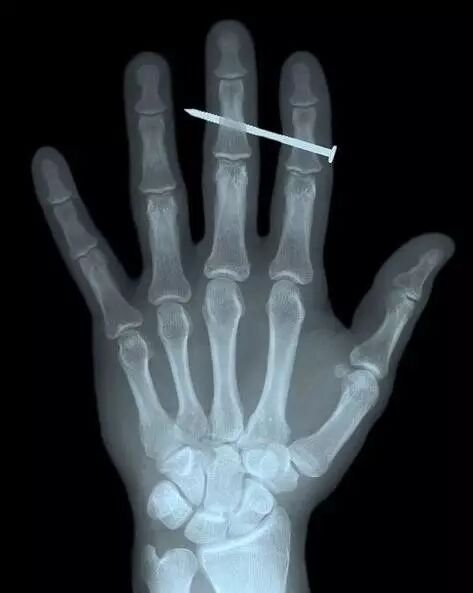

X射线照射人手和铁钉的影像[2]